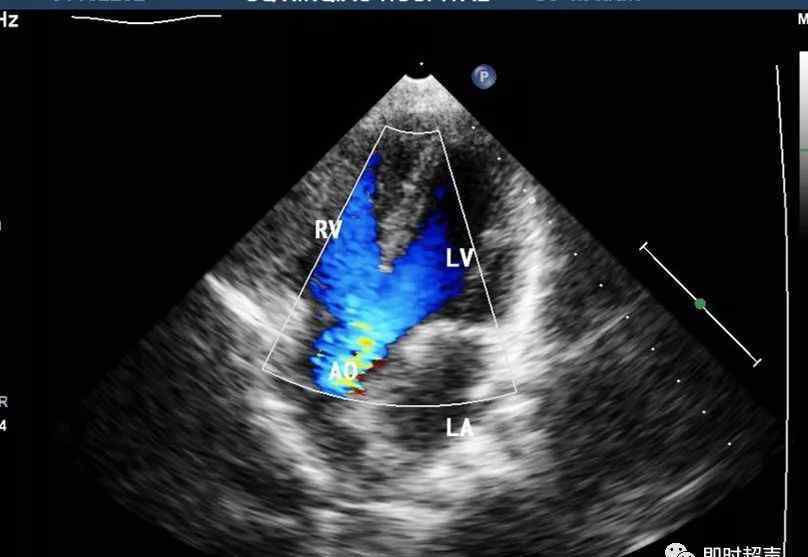

彩色多普勒血流显像(CDF I)(1)

来自左右心室的两个蓝色血流信号分别进入心尖五腔切面的主动脉。

彩色多普勒血流成像(CDFI-2)

室间隔中断处可见红蓝分流双向流程图。由于左右房室的压差较小,分流一般为层流。